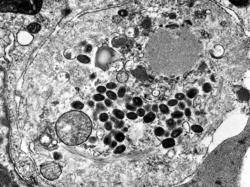

Credit: U.S. Centers for Disease Control

Contrary to the belief that smallpox is gone, there are at least two places where the virulent virus can be found. It is locked away in secure laboratories in Atlanta and the Russian city of Novisibirsk in Siberia. Pressure is mounting on the U.S. and Russia to destroy all remaining samples of the...